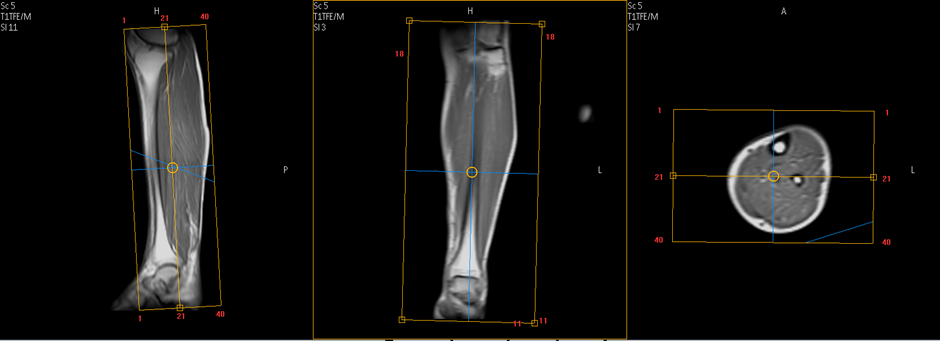

LEG

Position of patient: Supine feet first.

Supporting pad fix just below the legs.

Centering on mid leg.

Sequence- Survey three plane

Sequence

Cor- STIR,GRE,T1,T2

SAG-STIR

AXIAL- T2 FS,T1

Transverse plan: On coronal image plan block perpendicular to shaft of tibia and check block position on other planes with appropriate angle.

Sagittal plan: On coronal image plan block parallel to shaft of tibia and check block position on other planes with appropriate angle.

Coronal plan: On Sagittal image plan block parallel to tibia or fibula shaft   and check block position on other planes.